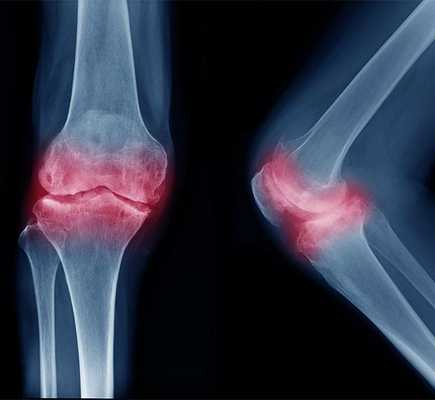

Субхондральный склероз коленного сустава

Наиболее важным диагностическим инструментом при остеоартрите, связаным со склерозом, является визуализирующее исследование - рентген. С его помощью врач, обычно ревматолог, может определить степень тяжести и тип склероза.

- патологические изменения в суставе, видимые на рентгенограмме, заключающиеся в сужении суставной щели или дефектах полых костей, так называемых костных геодов;